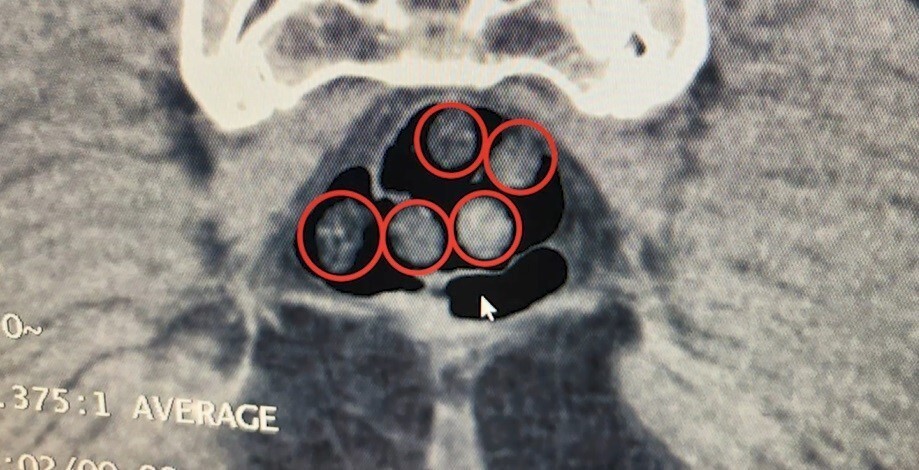

Diğer operasyonda ise Tatvan’da durdurulan bir otobüste yolcu olarak seyahat eden yabancı uyruklu 2 şahıs yakalandı. Tatvan Devlet Hastanesinde yapılan röntgen ve tomografi incelemelerinde, şahısların mide ve bağırsaklarında çok sayıda yabancı cisim tespit edildi. Tıbbi müdahale sonucunda şahısların yuttuğu 14 kapsül ile üzerlerinden çıkan 36 kapsül olmak üzere toplam 50 kapsül ve 385 gram metamfetamin ele geçirildi.

Valiliğin açıklamasında, "Tatvan’da durdurulan çekici üzerindeki araçta yapılan aramada; 734 gram metamfetamin maddesi ele geçirildi. Olay ile ilgili 2 şahıs gözaltına alındı. Yine Tatvan’da durdurulan bir otobüste yolcu olarak seyahat eden yabancı uyruklu 2 şahıs gözaltına alındı. Tatvan Devlet Hastanesinde yapılan röntgen ve tomografi incelemelerinde, şahısların mide ile bağırsaklarında çok sayıda yabancı cisim tespit edildi. Yapılan tıbbi müdahale ile şahısların yuttuğu 14 kapsül ve üzerlerinden 36 kapsül olmak üzere toplam 50 kapsül 385 gram metamfetamin maddesi ele geçirildi. Her iki olayda da uyuşturucu madde imal ve ticareti suçundan gözaltına alınan 4 şahıstan 3’ü çıkarıldığı adli mercilerce tutuklandı. Hemşehrilerimizin huzuru ve güvenliği için uyuşturucu madde imalatı, kaçakçılığı ve kullanımına karşı yürütülen kararlı mücadelemiz devam edecektir" ifadelerine yer verildi.

TATVAN DEVLET HASTANESİNDE YAPILAN RÖNTGEN VE TOMOGRAFİ İNCELEMELERİNDE, ŞAHISLARIN MİDE İLE...